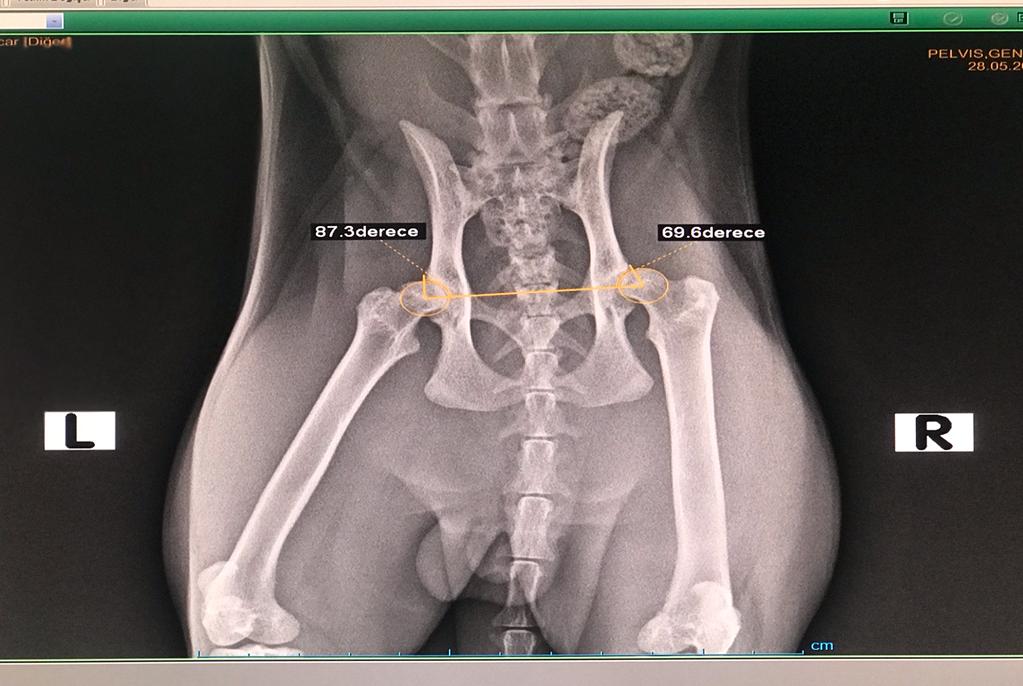

Kalça displazisi hastalığının en erken teşhisi 4 aylıkken gerçekleştirilen özel bir görüntüleme yöntemiyle mümkün olur. Pensilvanya üniversitesi tarafından geliştirilen bu sistemde 4 aylık köpeklerde anestezi altında ve özel bir aparat yardımıyla çekilen röntgenler ve yapılan ölçümlerle kalça eklemindeki esneklik katsayısı hesaplanmakta ve kalça displazisi riski ortaya konmaktadır. 4 aylıkken hastalığın saptanamadığı köpeklerin ise 6 aylıkken mutlaka kalça röntgenleri çekilerek kalça displazisi yönünden kontrol edilmeleri ve bu köpeklerin displazik olmadıklarına emin oluna dek periodik radyografik incelemelerine devam ediniz.

6 aylıktan daha büyük, kemiksel gelişimini tamamlamamış, kalça eklemlerinde dejeneratif eklem hastalığı bulunmayan ve eklemde tam çıkık şekillenmemiş köpeklerde ise tüm dünyada en sık uygulanan teknik “TPO-Triple Pelvic Osteotomy” adı verilen bir tekniktir. Oldukça zor ve masraflı olan bu teknik başarıyla uygulandığında kalçanın tüm anatomik yapısını değiştirmekte ve hastalıkla ilgili tüm sorunları ortadan kaldırır.